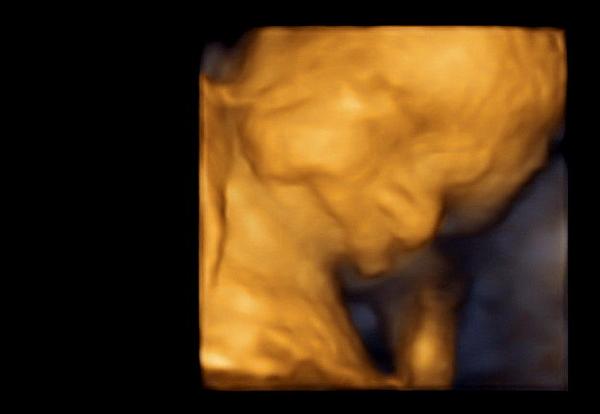

@esiii

Také jsem říkala,že něco koupím malým k Vánocům,tak mají bílá bodíčka se zvířátky.Dnes jsem byla také na ultrazvuku a prý bych se pohlaví mohla dovědět na další kontrole 14.12.Naši a nejbližší to už vědí,ale rodiče partnera se to doví také na Vánoce.Ty další Vánoce už budou ještě veselejší,to už budeme mít obě prcky u stromečku.-)